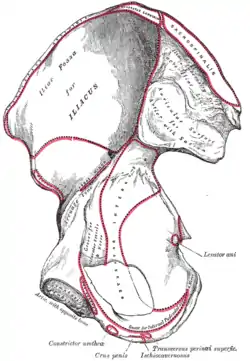

Position of iliacus muscle (shown in red.) Animation. Right hip bone. Internal surface. (Iliac fossa visible at upper left.)

Right hip bone. Internal surface. (Iliac fossa visible at upper left.)